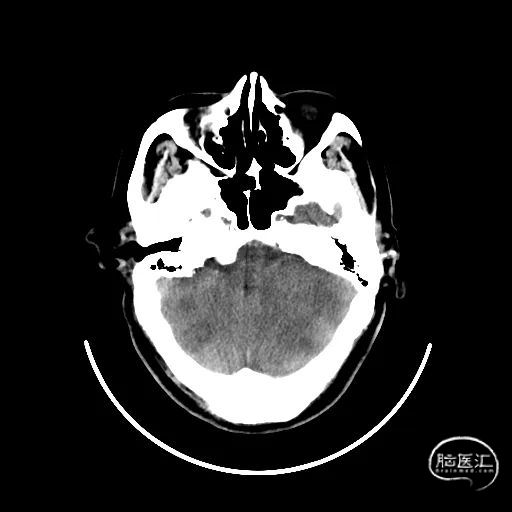

右侧颈内动脉起始部中度狭窄,未见血流向后循环代偿。

左侧颈内动脉造影提示后交通开放,代偿供应后循环。

左侧椎动脉开口重度狭窄,前向血流缓慢,V4闭塞。